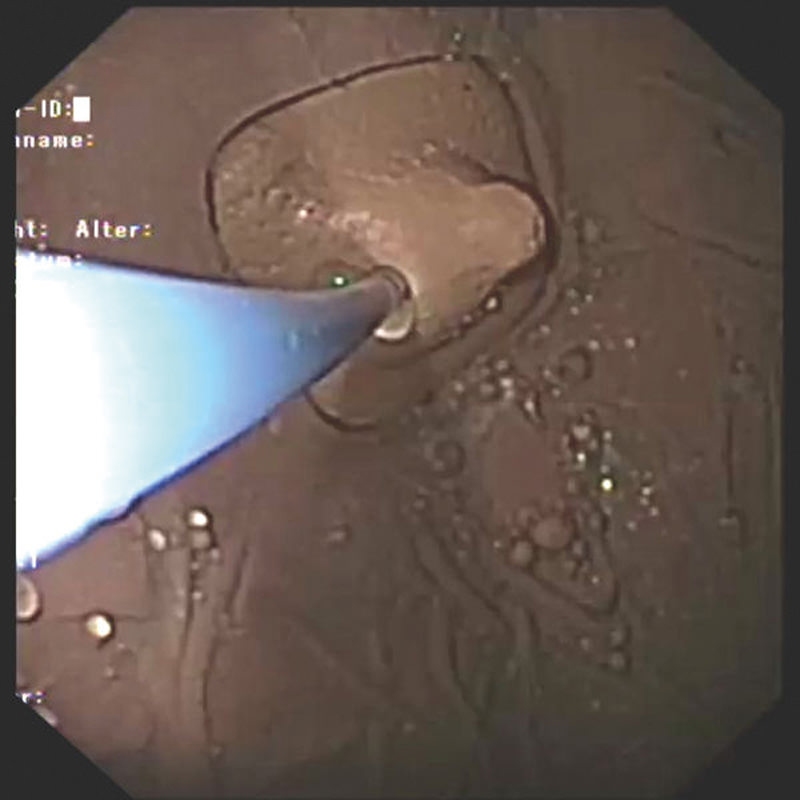

Simulator Gastro združuje možnosti realističnega anatomskega modela in usposabljanja za intervencijsko endoskopijo. Veliko število različnih vložkov omogoča zdravljenje polipov, kot so vbrizgavanje, dvigovanje, rezanje in odstranjevanje, simulacija zaustavitve krvavitve, stentiranje in drugo. Simulator in vložki so izdelani iz popolnoma umetnega materiala.

- Vadba vbrizgavanja tkiv

- Zdravljenje krvavitev / zaustavljanje krvavitev z injekcijami, sponkami in ligiranjem traku